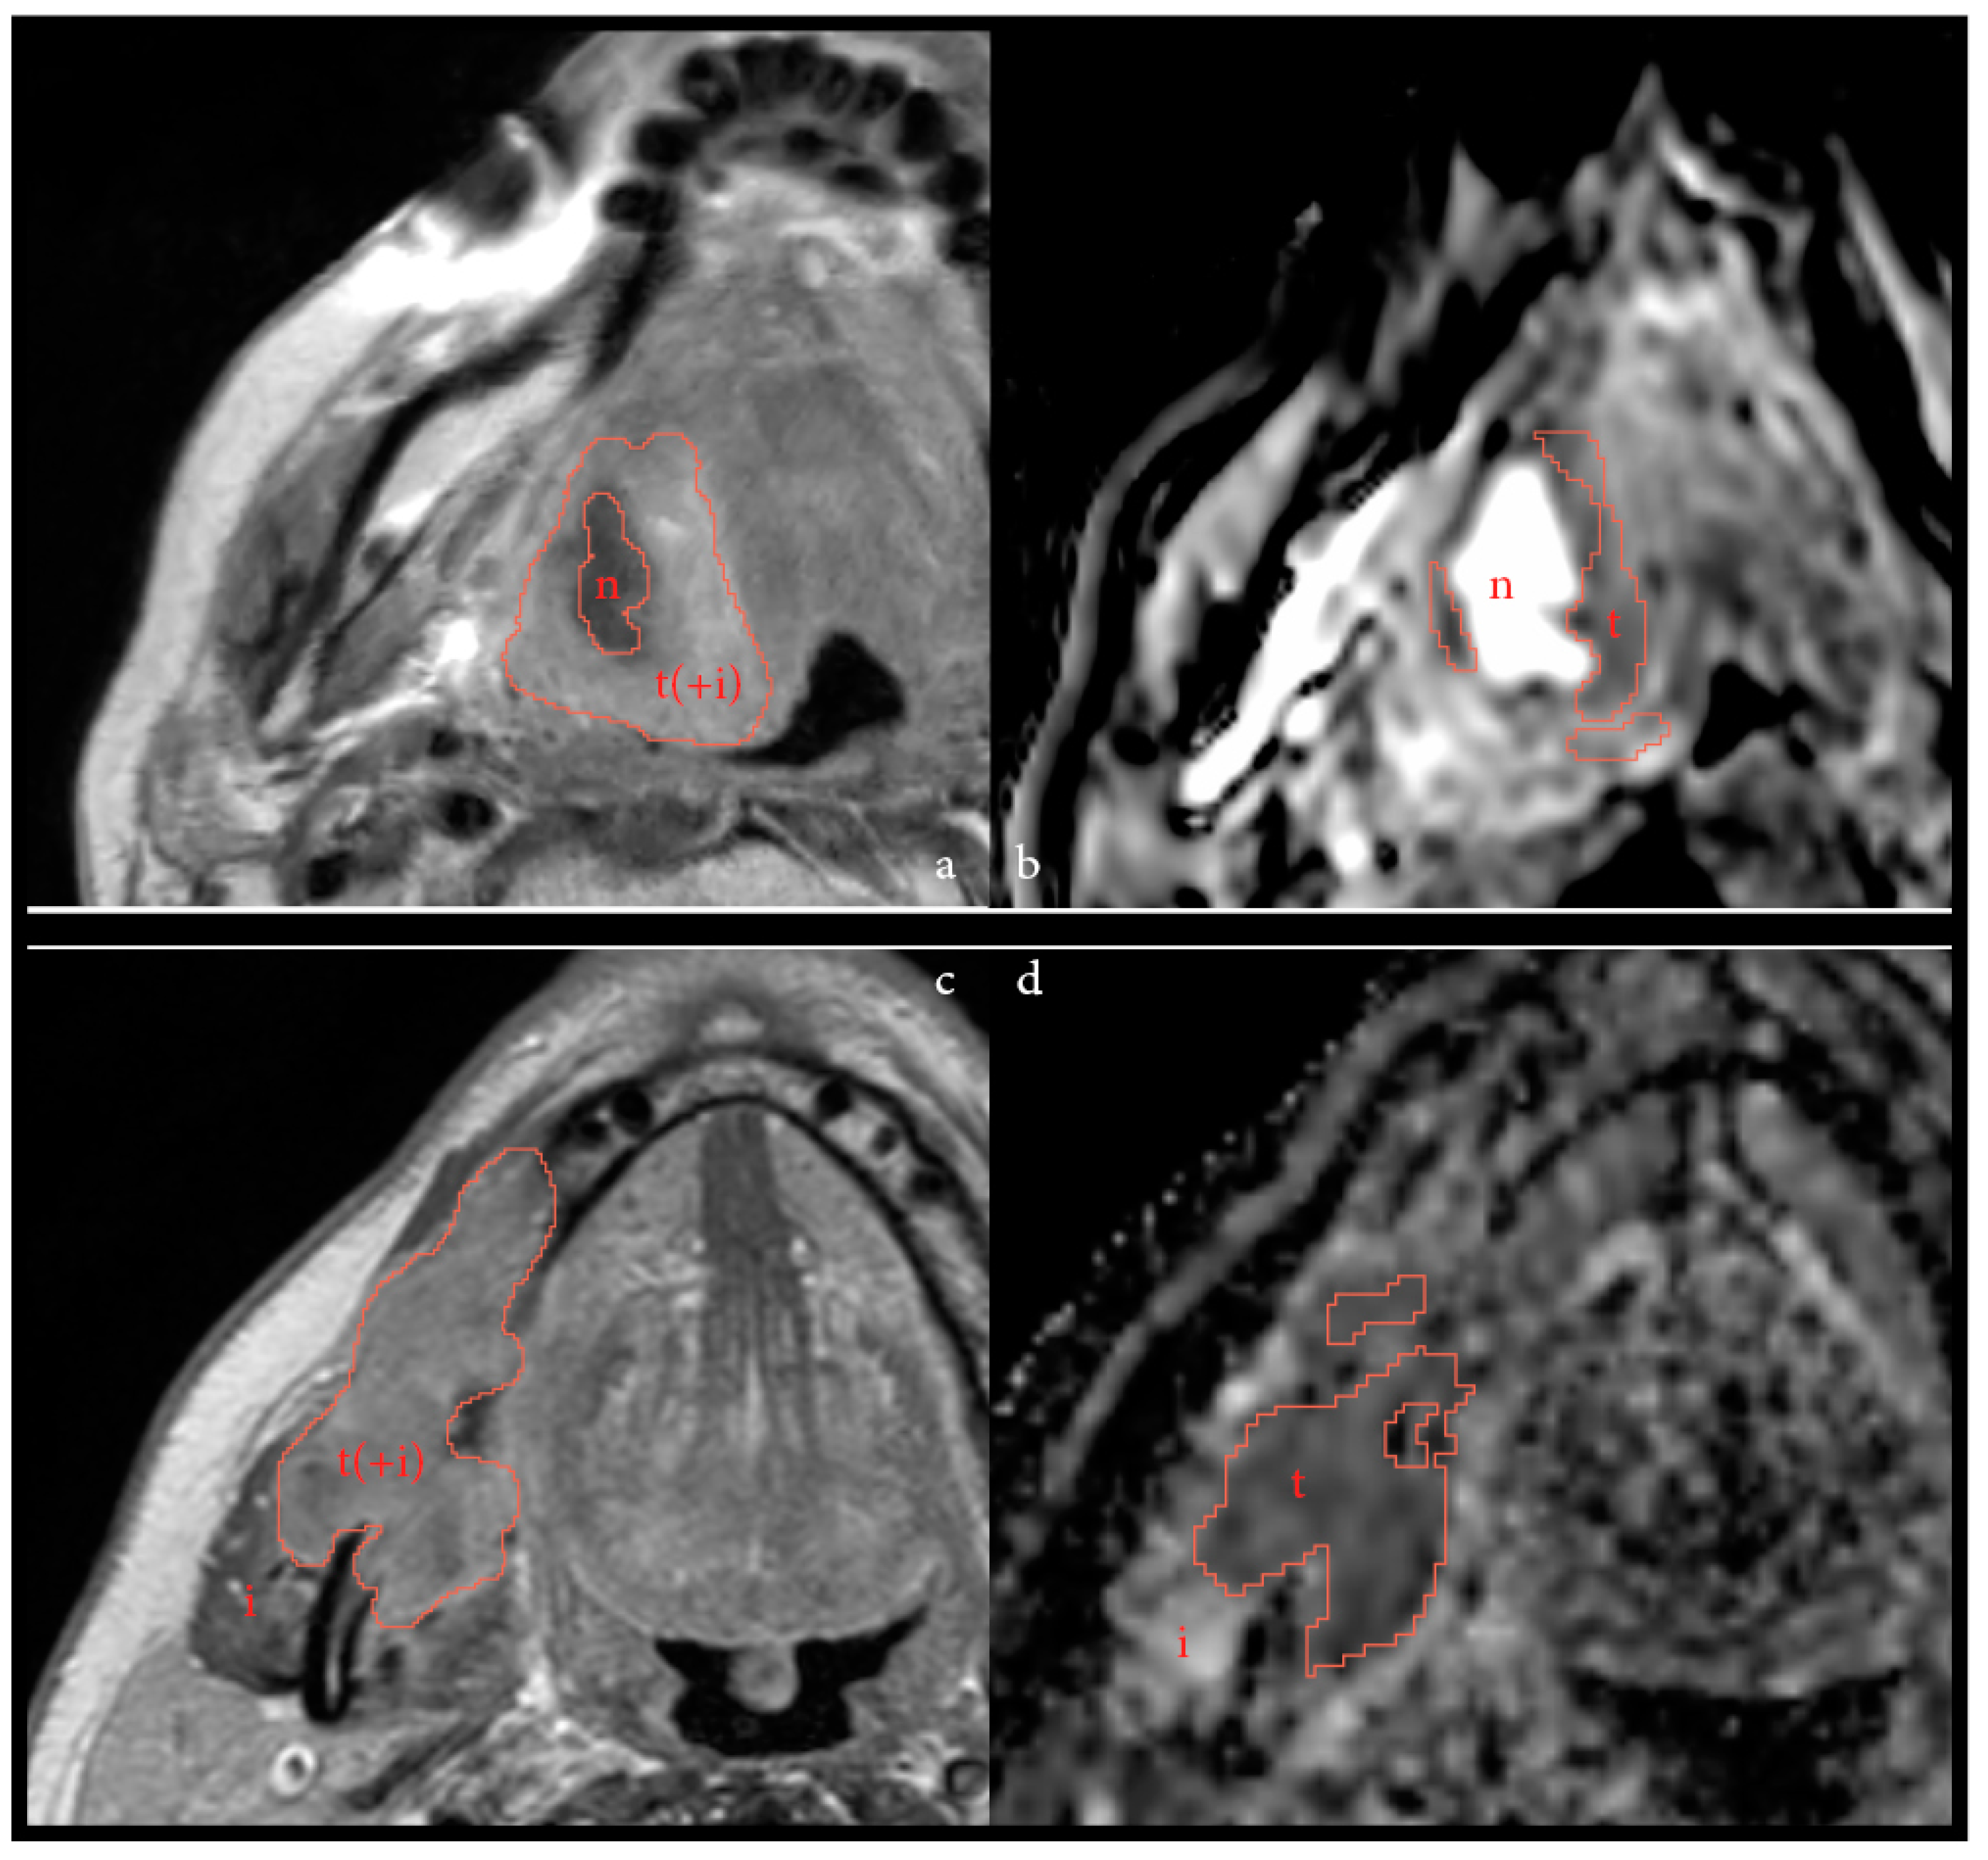

2.3. Postprocessing and Feature Extraction